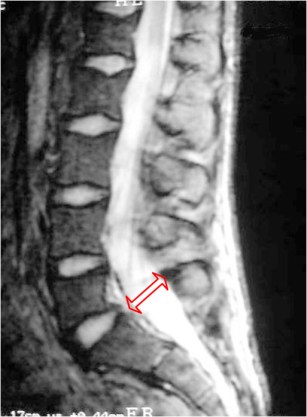

El aumento del diámetro anteroposterior del canal espinal en cortes sagitales de línea media en resonancia magnética se ha descrito como signo de espondilolistesis por espondilolisis, a diferencia de la espondilolistesis degenerativa.

El corte axial confirma el aumento del diámetro anteroposterior del canal y la espondilolisis L5 bilateral (bandas hipointensas marcadas con las flechas).

Aunque el signo se describió en RM, también es visible en las reconstrucciones sagitales de TC. El artículo que describe el signo es: Ulmer, JL y cols. Distinction between degenerative and isthmic spondylo-listesis on sagittal MR images: importance of increased antero-posterior diameter of the spinal canal («wide canal sign»). AJR 1994; 163: 411-416.